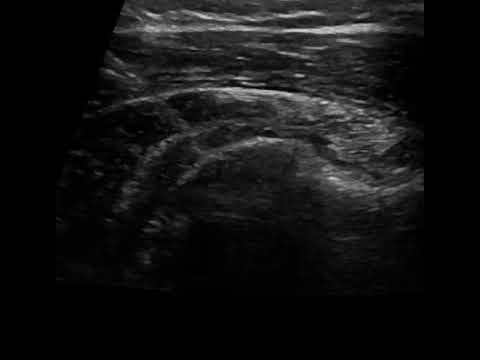

Κατά τη θεραπεία Barbotage γίνεται, με χορήγηση τοπικής αναισθησίας και υπό υπερηχογραφαγική καθοδήγηση, έκπλυση των ασβεστώσεων με φυσιολογικό ορό και έγχυση αντιφλεγμονώδους φαρμάκου στον υπακρωμιο-υποδελτοειδικό θύλακο του τένοντα.

Χάρη στην υπερηχογραφική καθοδήγηση, το Barbotage είναι μια αποτελεσματική και απόλυτα ασφαλής διαδικασία. Η χρήση του υπερήχου εξασφαλίζει τόσο την αποφυγή ζωτικών σημείων, όπως αγγείων και νεύρων, όσο και τη στοχευμένη έγχυση του θεραπευτικού μέσου ακριβώς στο σημείο των ασβεστώσεων, όπου χρειάζεται.